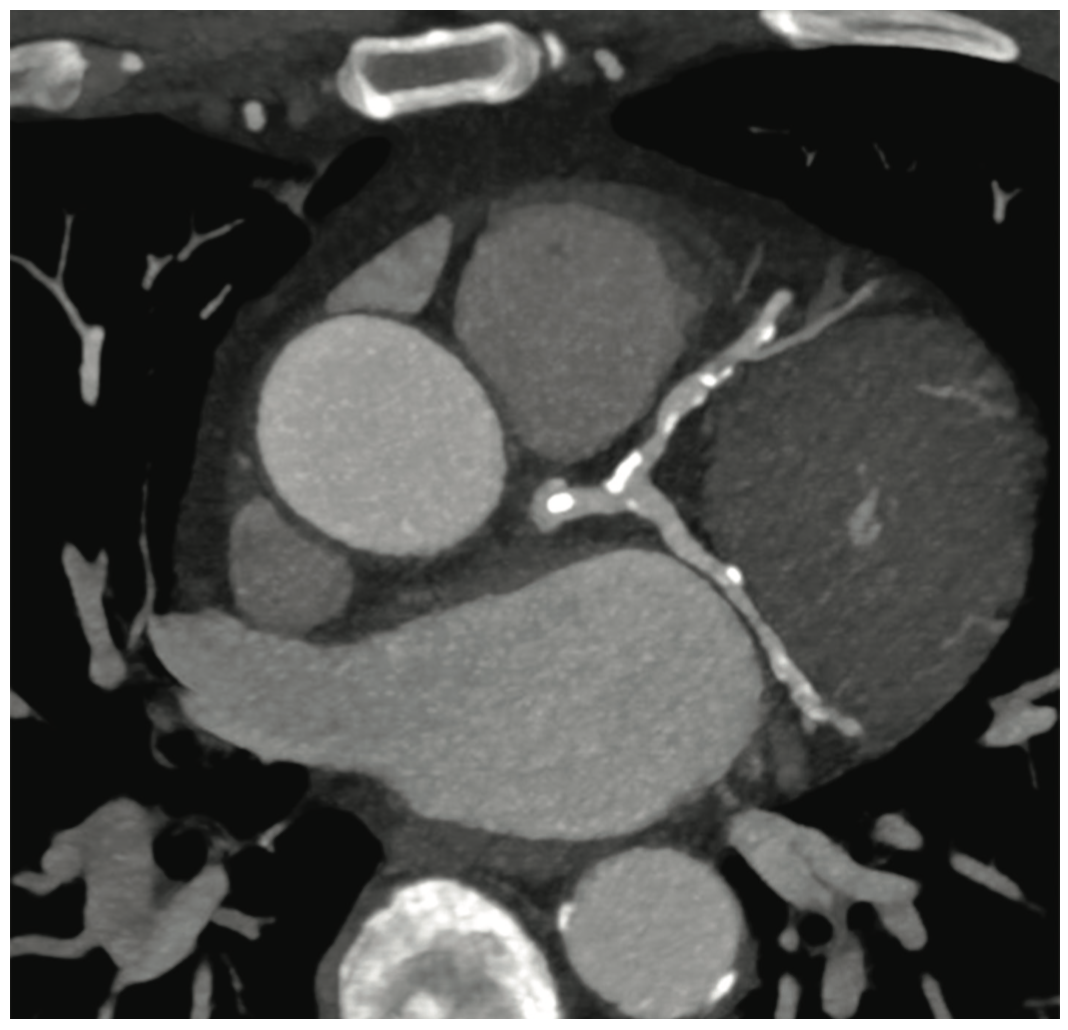

During an outpatient visit, a 73-year-old male presents with symptoms of chest pain on exertion. Physicians perform a coronary computed tomography angiogram (cCTA) using a dual source CT system (the SOMATOM Drive from Siemens Healthineers) that enables fast temporal resolution (75 ms) cardiac examinations. The presence of considerable calcifications, plaque, and vessel narrowing prompts the use of noninvasive FFRCT analysis software (from HeartFlow) to assess the effect on coronary flow. The FFRCT analysis indicates a drop in flow in the left circumflex artery (LCX) at levels that may suggest the need for intervention.